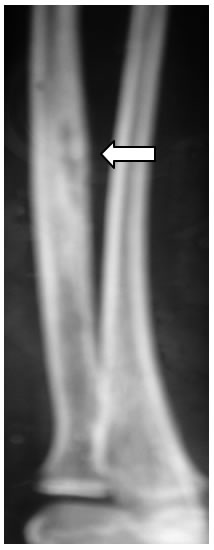

La ragazza è stata posta in trattamento per pochi mesi con apparente risultato iniziale, ma suc-cessivamente nonostante le infusioni la malattia riprende con dolori e un marcato peggioramento del quadro radiografico della sola lesione radiale destra (reazione periostale significativamente aumentata rispetto all'esame eseguito precedentemente, (figura 6)

Figura 6: reazione periostale significativamente aumentata rispetto all'esame eseguito precedentemente

L'entità dell'ultimo rilievo radiologico radiale è talmente impressionante che ripropone per l'enne-sima volta il dubbio di malignità.

In discussione collegiale con il radiologo, l'ortopedico e il reumatologo decidiamo per una seconda biopsia ossea che mostra ancora solo aspetti rigenerativi, escludendo una malignità.